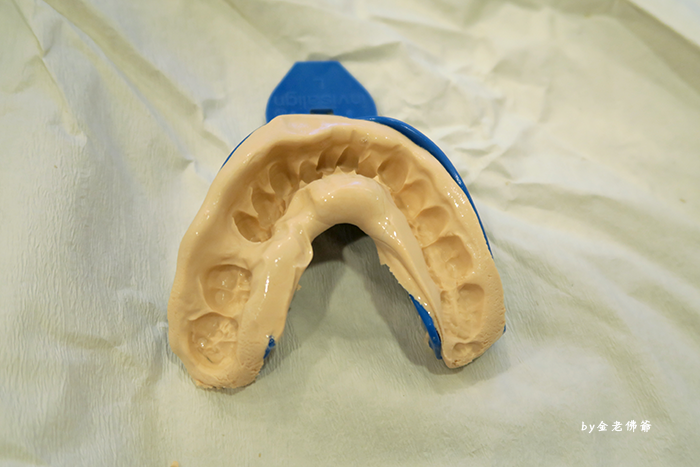

傳統製作模型

製作模型的時候

通常會給大家帶來不舒服的感覺

但這是沒有辦法的

因為這個模型是需要

用 UPS 快遞到美國去

(上面有提過隱適美 Invisalign 牙齒矯正的關係)

這樣一個月後才能知道成果

並且完成矯正器

做模型傳統的方式

總共要做總共4次 (牙齒上下各2次) 印出牙齒模型

過程中容易讓牙齒矯正的人

感覺到不舒服

第一次的時候會取出基本形狀

當作骨架

這個基本骨架是當作牙齦

會把細節先處理掉

然後再一次取出比較精準的模型

醫生必須先把細節磨掉

不過曹醫生會直接在旁邊處理

這個材質一開始很軟

但會越來越硬

處理完之後

會再用這個綠色的

來做牙齒的模型

這個材質可以把細節抓住

所以醫生把綠色的膏

放在剛剛的骨架上面

擠好以後

就是在讓矯正的MIU喔爸來體驗一下

這樣就會取出正確的牙齒模型了

傳統的方式不只是印牙模

還要拍照